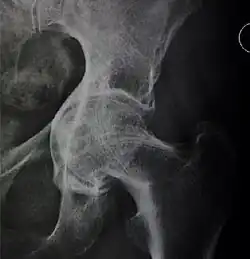

X-ray of hip dysplasia